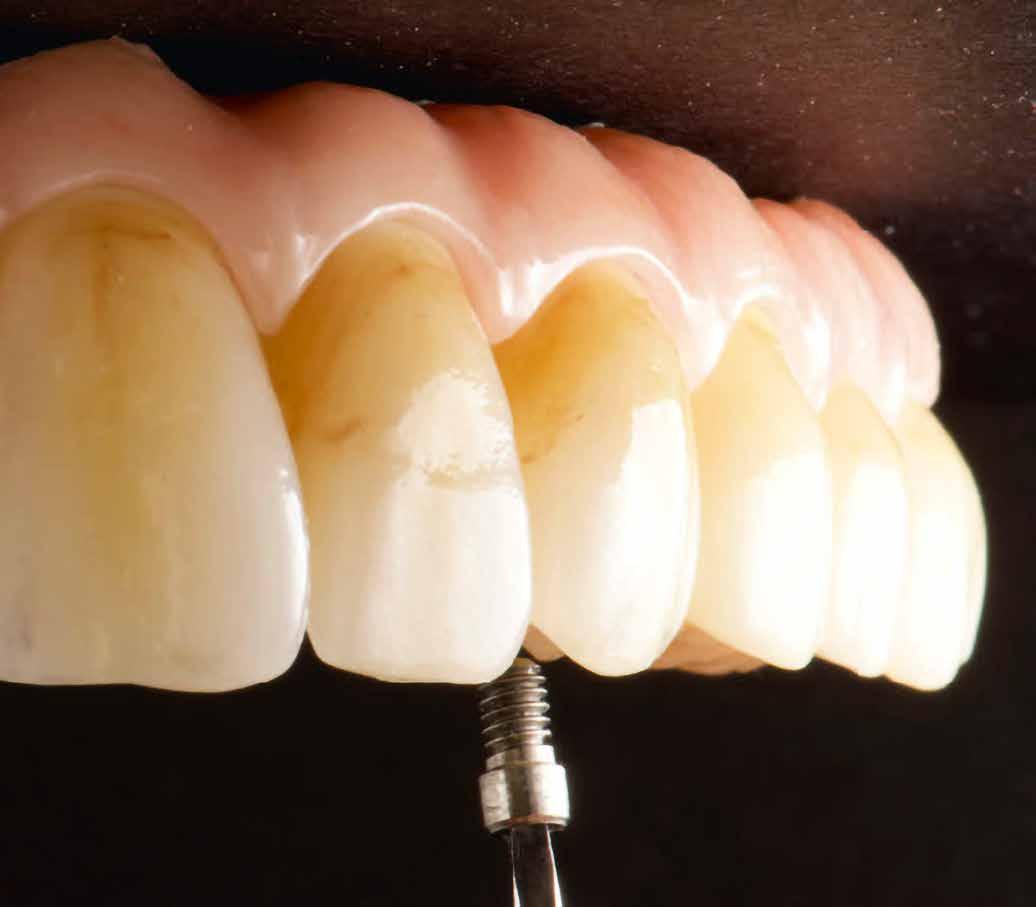

A biológiai orvoslás a pácienst helyezi a középpontba a mindenkori fogorvosi és fogtechnikai eljárások és az azokból képzett konzekvenciák vonatkozásában. Időközben már bizonyított tény, hogy az emberi testbe helyezett fém jelenléte a legrövidebb időn belül a vérképben is kimutatható. Éppen ebben rejlenek a fogászatban, különösen az implantológiában nagy veszélyek. Mert ha még olyan nagy értékűek is a felhasznált anyagok, akkor is találhatók a tiszta titán felszínén is mikroszennyeződések. A fémek oldódhatnak a nyálban, lenyelhetők, a későbbiekben megváltoztathatják sejtjeink szerkezetét, ami elviselhetetlenséghez, autoimmun betegséghez vezethet. Dr. Dr. Michael Rak Bernriedből, illetve az augsburgi Highfield/Design cég Norbert Wichnalek vezette fogtechnikuscsoportja kifejlesztett egy olyan eljárásmódot, ami felel ezekre a kihívásokra, és a lehető legkevésbé terhelő módon látja el a pácienseket.

Dr. Dr. Michael Rak rendelőjében nem csak üres szó, hogy az ember áll a fogászati történések központjában. Minden a biológiai fogorvoslás terápiája körül forog. Az augsburgi Highfield/Design cég Norbert Wichnalek vezette fogtechnikuscsoportja évek óta foglalkozik a páciensek fémmentes megoldásokkal történő ellátásával. Ezeket erősítették Dr. Dirk Duddeck berlini CleanImplant Alapítványának tanulmányai is. Dr. Duddeck szerint sem a CE tanúsítvány, sem a mégoly neves és nagy gyártó sem tudja garantálni, hogy az implantátumokon ne legyen idegen részecske. Majd 15 éve vizsgál steril csomagolású implantátumokat pásztázó elektronmikroszkóppal. Ezalatt 300 különböző implantátumot vizsgált 200 gyártótól, alaposan analizálva azokat. A 2017 és 2019 közötti vizsgálat, amelyet a berlini Charité Egyetemmel együttműködésben folytatott, megmutatta, hogy szinte minden harmadik, tiszta környezetben kicsomagolt és PEM vizsgálatnak alávetett implantátumminta jelentős szennyezéseket tartalmaz. A steril implantátumfelszínen vas, króm, molibdén, réz, ón, volfrám és nikkel, valamint szerves szenynyeződés is kimutatható volt, még műanyagok jelenléte is. A szennyeződések az implantátumfelszínen, különösen a szerves anyagok jelenléte a gyártási és csomagolási eljárás alatt azt a gyanút ébresztik, hogy fennáll a dentális implantátum nem megfelelő csontosodásának veszélye, illetve felelős lehet a korai csontosodási fázis csontveszteségéért is. 2017 óta a CleanImplant Alapítvány bevezetett egy nemzetközileg elismert vizsgálati eljárást, aminek eredményeképpen a tiszta felszín és megfelelő klinikai dokumentáció esetén elérhető a „Trusted Quality Mark” (megbízható, minőségi gyártmány – a ford.) kitüntetés. Néhány hónap alatt több mint 125 ezer fogorvos csatlakozott a Facebook-on a CleanImplant Alapítvány minőségi kezdeményezéséhez. Azóta is havonta több mint ezer felhasználó keres megbízható információkat a nem terhelő implantátumrendszerekről a projekt honlapján. Az itt bemutatásra kerülő pácienseset megoldása során a szintén

„Trusted Quality Mark”-kal kitüntetett SDS implantátumokat használták – nem véletlenül – Dr. Dr. Michael Rak rendelőjében. A szerzők még egy lépéssel tovább mentek, és a kezelés neuralgikus pontjain a plazmakezelést is alkalmazták.